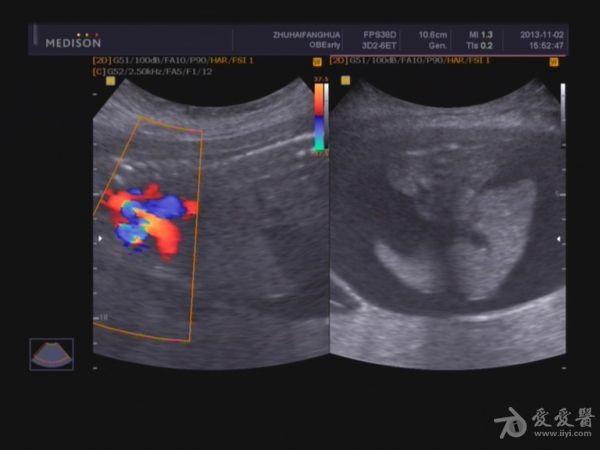

脐带:结构正常,脐动脉血流参数:SPV:33cm/s,PI:1.0,RI:0.62,S/D:2.6。典型图片如下:

2.胎儿畸形,胸、腹腔大量积液,

3.超大胎盘,羊水少。